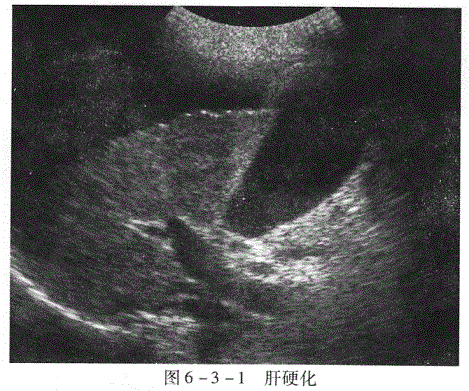

声像图表现(图6-3-1):

1.肝实质回声 早期肝实质回声改变不明显。中晚期肝脏回声弥漫增强和增粗,分布不均匀,部分病例可观察到0.3~1.5cm左右的肝再生结节,多呈圆形或形态不规则的低回声,周围常有高回声带包绕,与肝癌很难鉴别。

2.肝脏大小、形态和肝表面 肝硬化早期肝脏增大,但形态正常,肝表面尚光滑。中晚期肝脏萎缩、变形,以肝右叶萎缩明显,肝脏表面不平,呈小锯齿状或凹凸不平。

3.肝静脉 肝静脉变细、管径粗细不一,走行迂曲或显示不清,甚至闭塞消失。

4.门静脉高压征象

(1)门静脉主干及属支内径增大,门静脉内径>13mm,脾门处脾静脉内径>9mm,脾静脉走行迂曲。

(2)脾肿大 多为中度或重度肿大。

(3)腹腔积液较少时,平卧可在盆腔,肝肾隐窝处见无回声,较多时,在两侧膈下、

两侧腹及盆腔见到大片无回声,无回声内可见肠管漂浮。

(4)胆囊壁增厚因低蛋白血症、腹腔积液、门静脉压力升高或淋巴回流受阻等原因,

胆囊壁均匀性水肿增厚。

(超声所见:肝脏回声增粗增强,肝表面呈锯齿样,肝前可见无回声。)